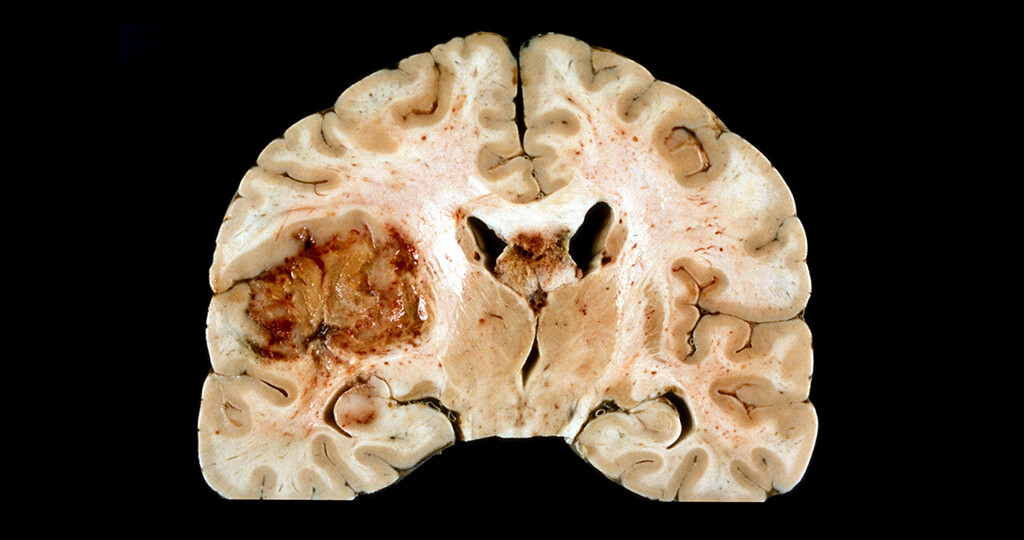

Микрофотографии гистологии глиобластомы головного мозга